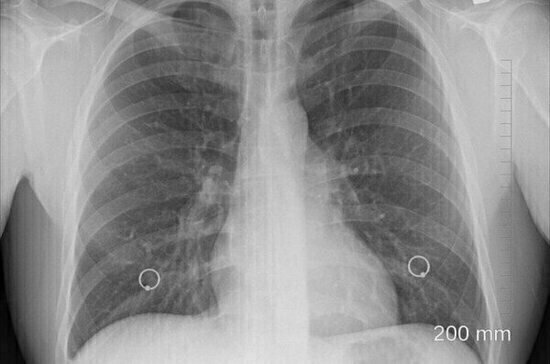

Самым известным и распространенным признаком онкологического заболевания лёгких является постоянный кашель. Об этом говорится в заявлении британской Организации по исследованию рака, которое опубликовано в журнале Express, пишет «360».

Учёные отмечаются, что кашель, если у больного развивается рак, может сопровождаться болью и кровохарканием.

Кроме того, признаком наличия злокачественных образований в лёгких может стать одышка и боль в грудной клетке. Людям также стоит насторожиться, если они теряют аппетит, у них резко снижается вес, преследует постоянное чувство усталости и учащаются инфекции грудной клетки. В этом случае медики советуют как можно быстрее пройти обследование.